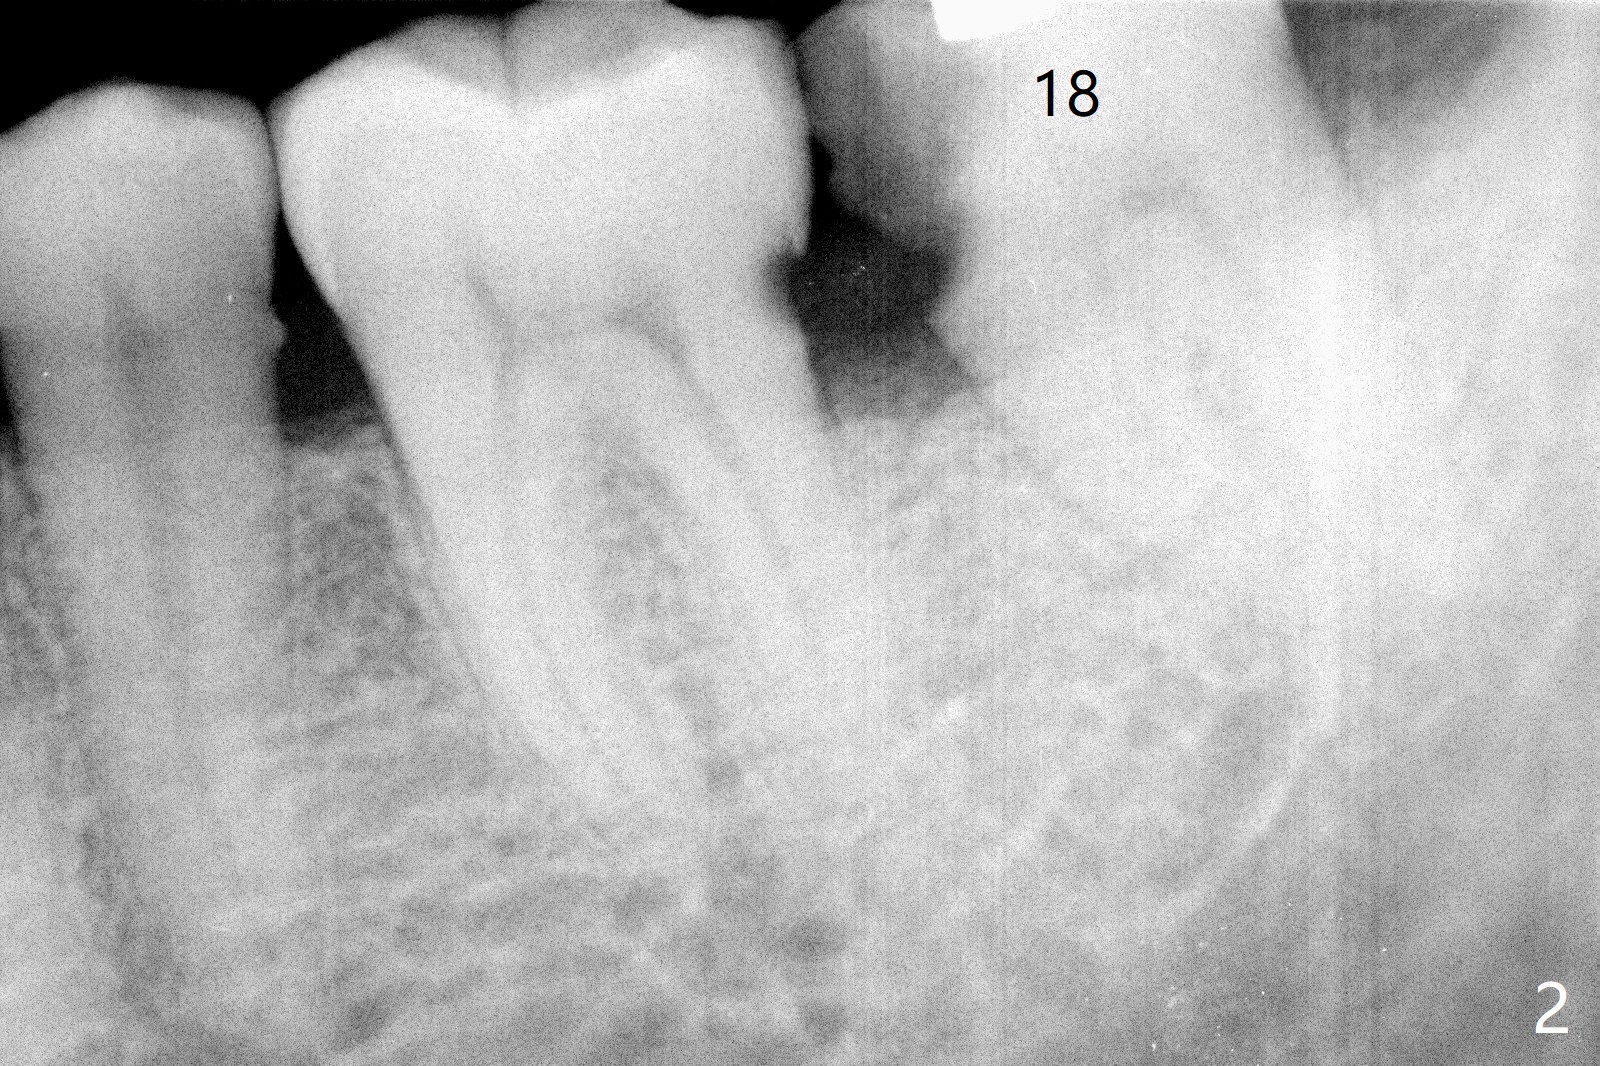

72岁男4.5前左上第二磨牙位置正常(图一),当时左下第二磨牙龋齿严重(图二),后来在别的诊所拔除,最近回来要求左上第一磨牙(图三)和左下第二磨牙种植(图四),由于左上第二磨牙延申(图五),为了左下第二磨牙导板种植,左上第二磨牙近中舌侧牙尖必须磨除不少(图三:*),总之,第二磨牙导板延期种植吃力,下午第二磨牙导板即种就没有这方面困难。